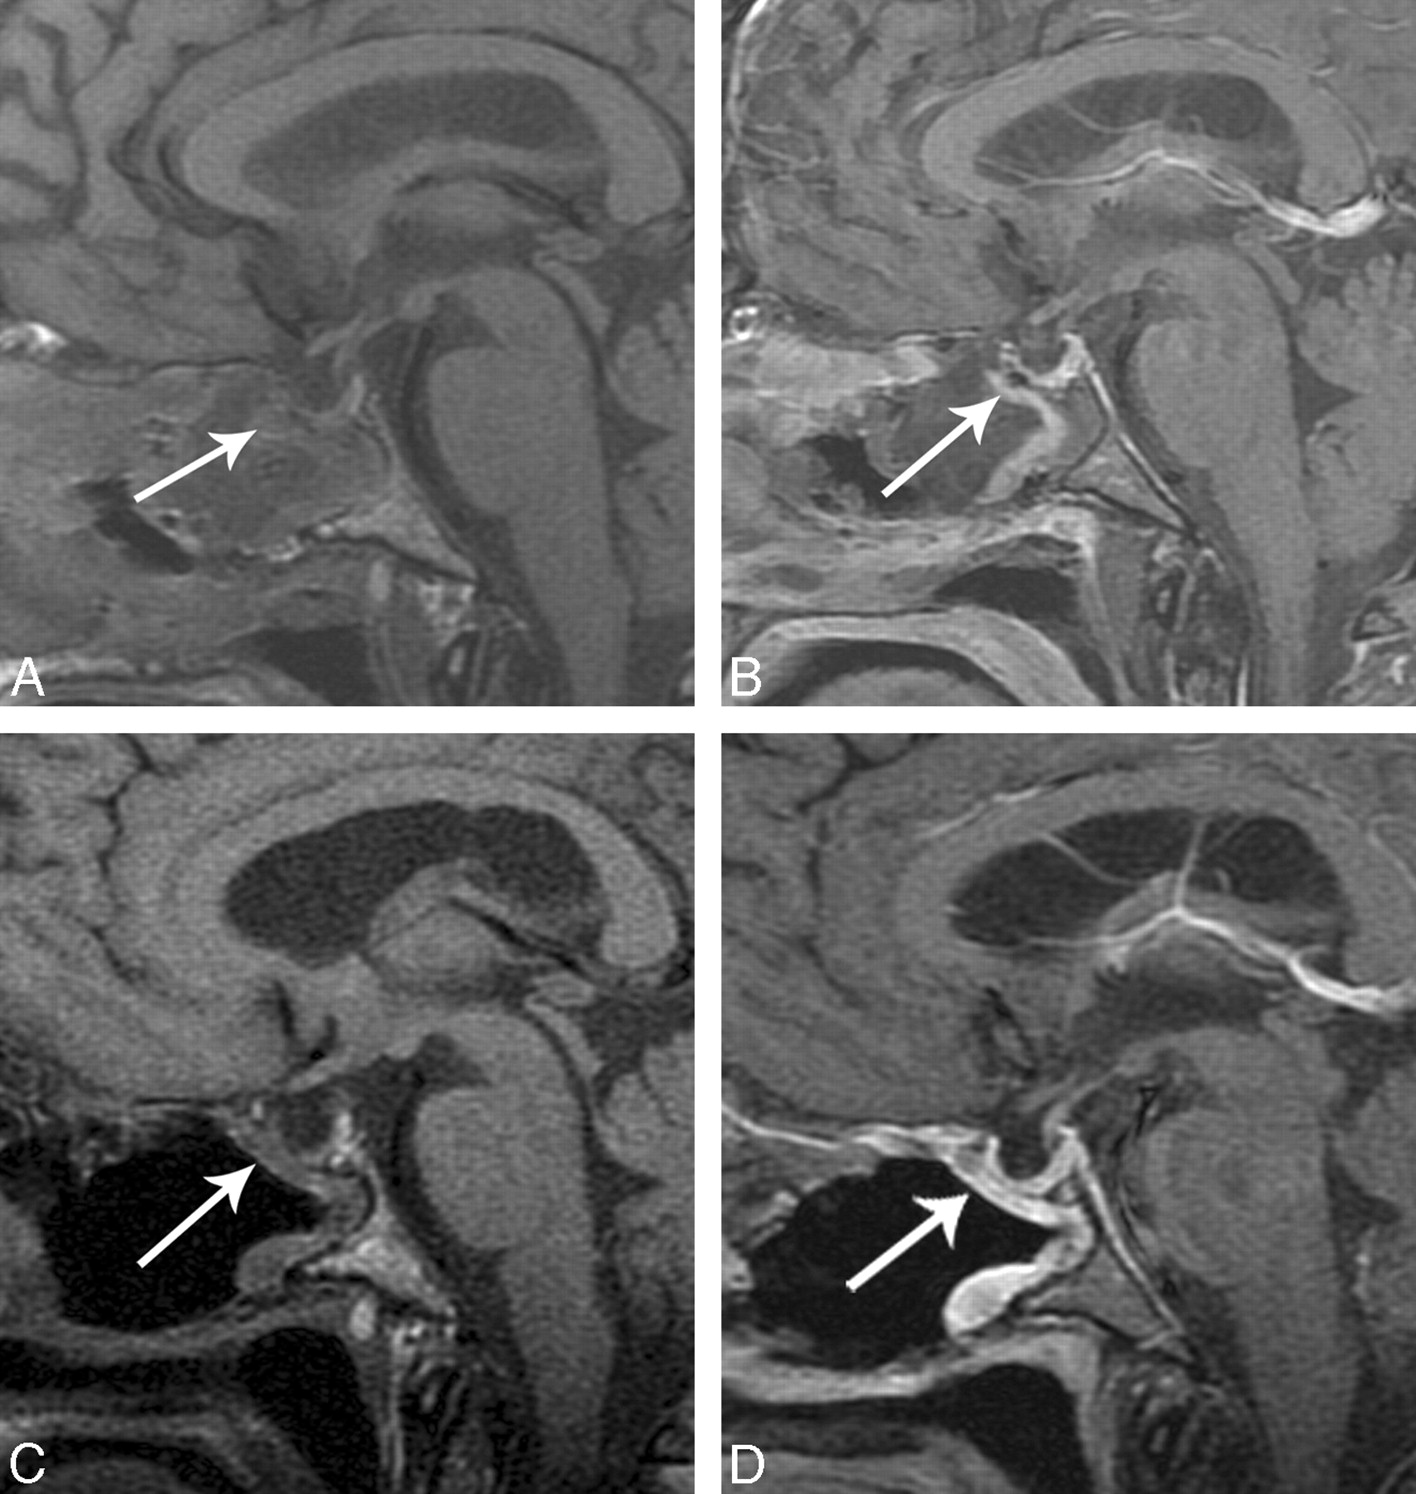

A, Immediate postoperative sagittal T1-weighted image shows a C-shaped flap underlying the operative defect (white arrow). B, Immediate postoperative sagittal T1-weighted image postcontrast with fat suppression shows a C-shaped flap underlying the operative defect (white arrow). C, Follow-up postoperative MR imaging scan sagittal unenhanced T1-weighted MR imaging shows decreased debris and removal of Foley catheter balloon in the sinonasal cavity and a C-shaped configuration of the flap, which is isointense (white arrow). D, Follow-up MR imaging sagittal T1-weighted postcontrast with fat suppression shows robust and thicker enhancement of the flap (white arrow).

The enhancement and average thickness of the flap in the immediate postoperative period can be variable (Table 2). There was mild enhancement of the flap in the immediate postoperative period in 1 of 10 patients, but on follow-up MR images, there was increased enhancement and thickness. Figure 5A shows a thin, enhancing C-shaped structure in the operative defect, which is thicker and more robust on follow-up MR imaging (Fig 5B). There was no appreciable enhancement on the immediate postoperative image (Fig 6A) in 1 of 10 patients. The follow-up MR imaging examination shows enhancement in the expected region of the flap (Fig 6B). A postoperative CSF leak did not develop in either of these patients.

The expected delayed postoperative follow-up MR imaging examination obtained at 3 to 7 months postoperatively (average, 4.5 months) showed resolution of the sinonasal cavity fluid and removal of the Foley catheter balloon. The signal intensity of the flap remained isointense on T1-weighted and T2-weighted sequences. The vascular pedicle nasoseptal flap was directly subjacent to the operative defect and may have been be thicker or thinner with enhancement. The thickness of the multilayer reconstruction between the graft and the defect is decreased, demonstrating decreased postoperative edema and involution of the packing material (Fig 5D).